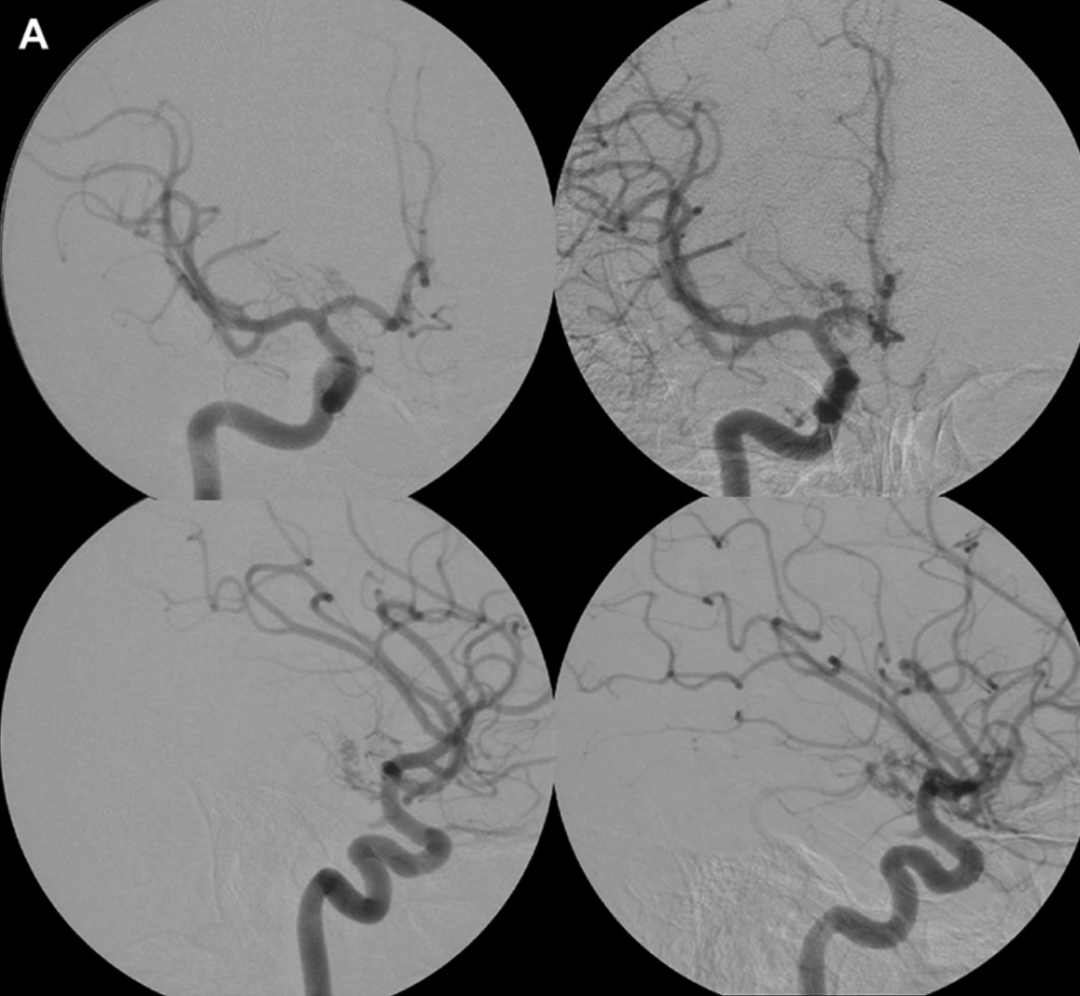

术前:经右侧颈内动脉(ICA)注射造影的脑血管正位(上图)与侧位(下图)诊断性血管造影片,显示颞叶内侧及视束存在由右侧脉络膜前动脉(AChA)供血的动静脉畸形(AVM)。